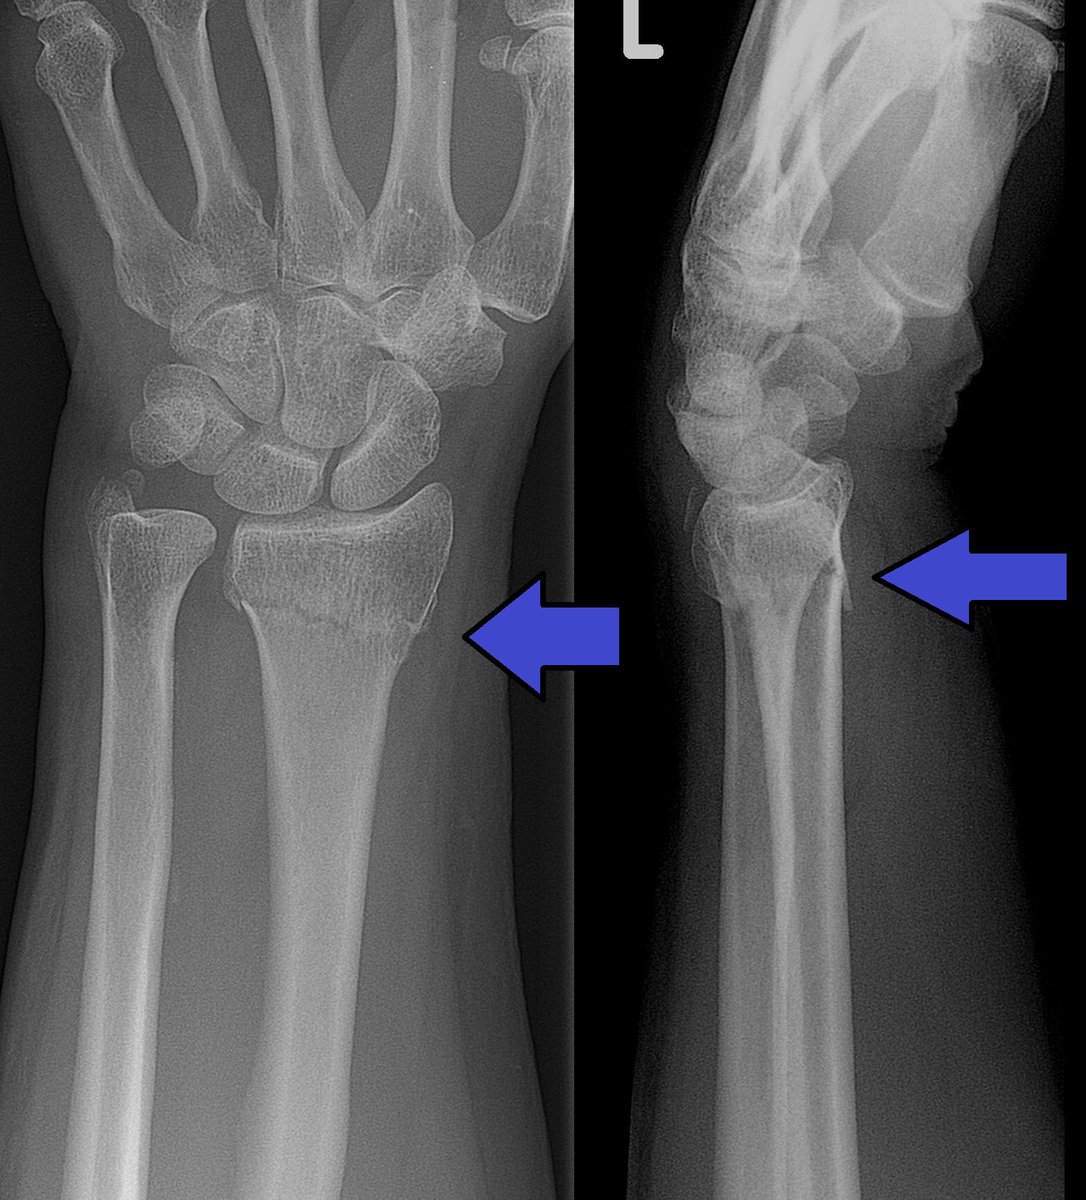

ايش هو ال colles fracture

هو كسر يحصل في ال radius bone لما الشخص يطيح ويحاول يمنع الطيحه بيده فيحمل ثقله كله على يده

هذا الكسر عادةً يسبب تشوه اسمه ال dinner fork deformity ? وسموه كذا لان يد المريض يسير شكلها زي الشوكة وسبب هالوضعية ان الشخص يطيح ويده واصابعه مفروده

ويعرف هالنوع من الاصابات بإسم FOOSH اختصارا لـ

"fallen onto an outstretched hand"